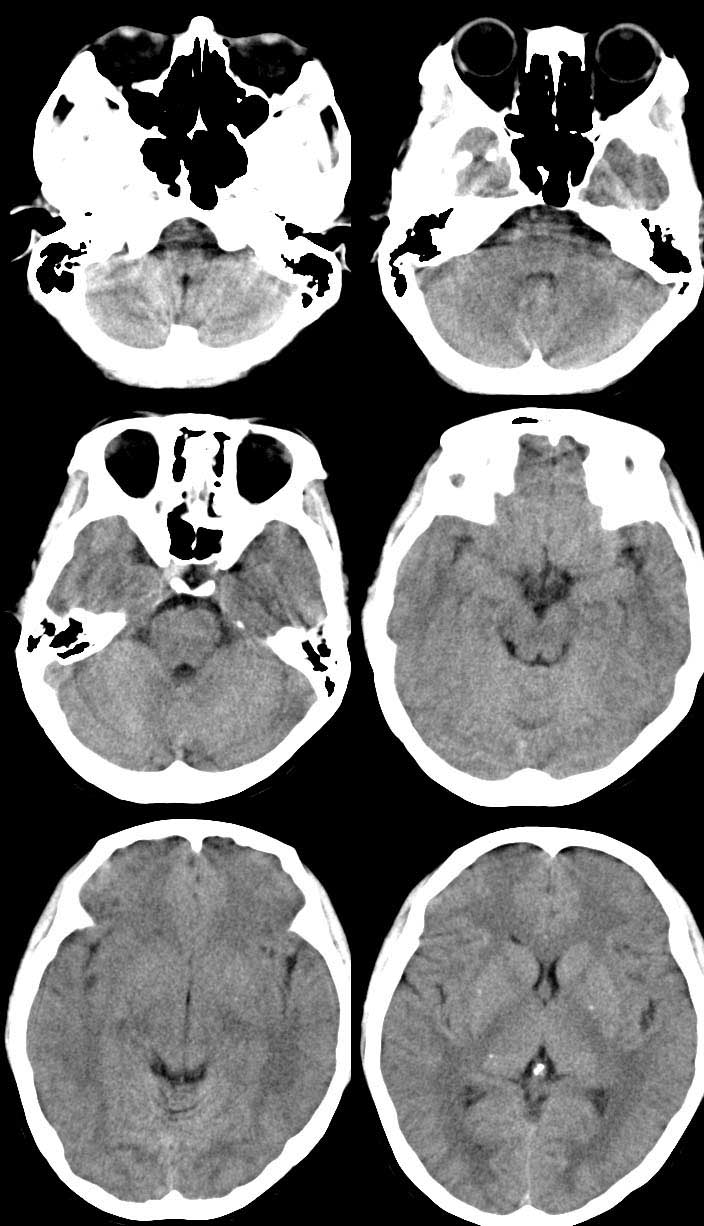

病人女 35岁 自述头晕 头痛

双侧基底节区及右侧丘脑区多发点状钙化,周围未见水肿及占位征象.余未见明显异常.考虑:脑囊虫病<囊虫的退变或死亡期>请结合有无相关病史.

颅内有散在钙化

脑囊虫病理性钙化。